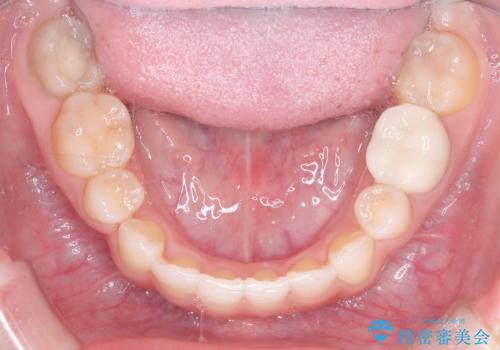

- 上下の前歯に激しい段差がある**重度の叢生(がたつき)**を主訴にご来院されました。精密検査の結果、歯をきれいに並べるためのスペースが圧倒的に不足していたため、上下左右の4番目の歯(第一小臼歯)を計4本抜歯する計画を立案しました。

本症例では、まず抜歯した大きなスペースを効率よく使い、歯の根元から大きく動かす必要があるため、初期段階にワイヤー矯正を採用。その後、細かな噛み合わせの調整や仕上げにインビザラインを使用する「ハイブリッドな矯正治療」で、期間の短縮と精度の高い仕上がりを目指しました。

ワイヤー矯正による先行治療: 最初のステージでは、ワイヤー装置を使用して抜歯したスペースへ歯を大きく移動させました。重度の叢生の場合、ワイヤーを用いることで歯のねじれや大きな移動をスピーディーに行うことができ、治療期間の短縮につながります。

インビザラインによる精密な仕上げ: 全体のがたつきが概ね整った段階で、インビザライン(マウスピース矯正)へ移行しました。透明で目立たないマウスピースを使用しながら、0.1mm単位の細かな歯の配置や、最終的な咬み合わせのバランスを精密に整えていきました。

治療の結果、重度のがたつきは跡形もなく解消され、抜歯したスペースもきれいに閉じました。ワイヤーによる「確実な移動」と、インビザラインによる「緻密な仕上げ」を組み合わせることで、審美性と機能性の両立を叶えた美しい歯並びを実現しました。